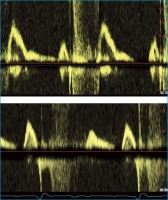

Diastolische Dysfunktion

Abbildung 2: Diastolische Dysfunktion. Strömungsprofil über der Mitralklappe: Oben normal, unten pathologisch, E/A 0,6 (E = early diastole, A = atrial contraction)

Keywords: diastolische DysfunktionHypertonieMitralklappe